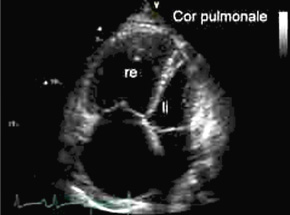

Echokardiographie (Vierkammerblick): Normalerweise sind die linke Herzkammer (rechts oben) und der Herzvorhof (rechts unten) größer als rechtsseitigen Herzhöhlen.  Beim Cor pulmonale sind die Größenverhältnisse aufgrund des erhöhten Drucks im rechten Herz seitenvertauscht.